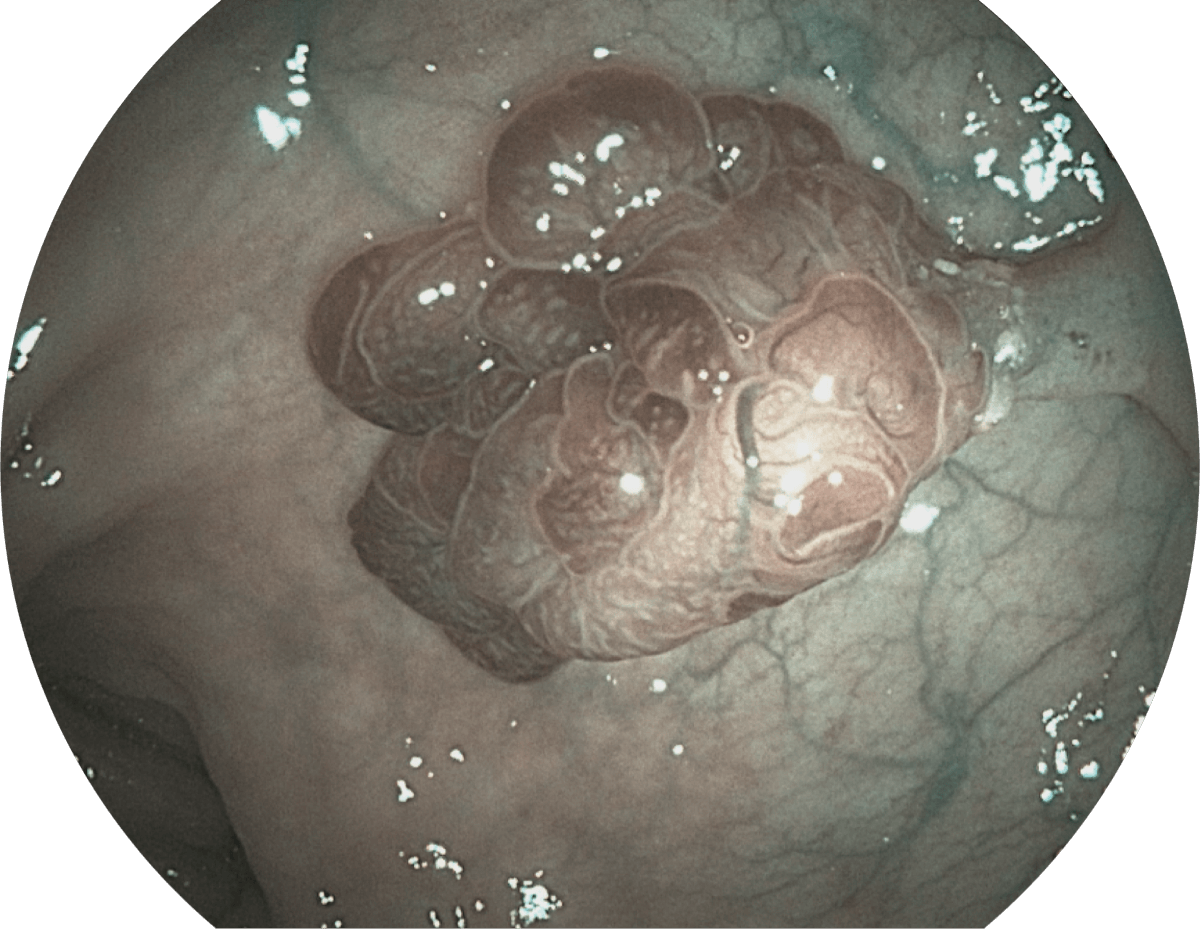

• WL

• SFI

• VIST

图像具有高亮度、高黏膜血管颜色对比度的特点,且不改变粘液、食物残渣、粪便的基本颜色,可在中远景下进行观察,助力消化道早期疾病的诊断。

强调浅层黏膜结构的同时,保证照明亮度和提升浅层微血管与中层血管颜色对比度,病变边界更清晰。